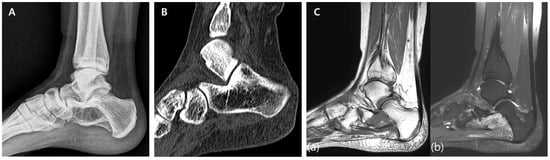

A 57-year-old female presented with right-ankle pain following a fall three weeks prior. Preoperative X-ray (Figure 5A) and CT scans (Figure 5B) demonstrated a heterogeneous hypodense mass measuring 15 × 27 × 41 mm, with irregular margins extending from the medial malleolus to the metaphyseal region of the distal tibia. MRI revealed a lobulated lesion with heterogeneous low-to-intermediate signal intensity in T1-weighted images, high signal intensity in T2-weighted images, and rim enhancement after contrast administration (Figure 5C). The lesion was provisionally diagnosed as low-grade chondrosarcoma based on the imaging characteristics observed.

Figure 5. Preoperative imaging. (A) Preoperative X-ray demonstrating a lytic lesion with well-defined margins in the tibia. (B) Preoperative CT scan showing the lesion’s cortical involvement and surrounding bone structure integrity. (C) Preoperative MRI. (a) T1-weighted image displaying a hypointense lesion within the tibia. (b) T2-weighted image showing heterogeneous hyperintensity with internal low-signal regions. (c) Contrast-enhanced T1-weighted image highlighting the lesion’s vascular characteristics.